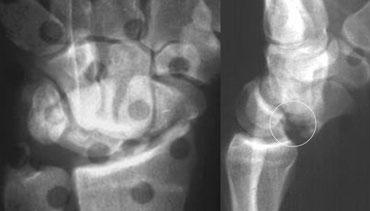

Các dấu hiệu này cho thấy đây là trật khớp quanh nguyệt kèm gãy xương thuyền và xương đầu (transscaphoid, transcapitate perilunate fracture-dislocation).

Bên trái là cùng một ca lâm sàng với đường kẻ chỉ ra đường gãy-trật khớp.

Cùng ca lâm sàng với tư thế chếch và tư thế nghiêng bổ sung, cho thấy tình trạng trật khớp ra phía sau (dorsal dislocation).